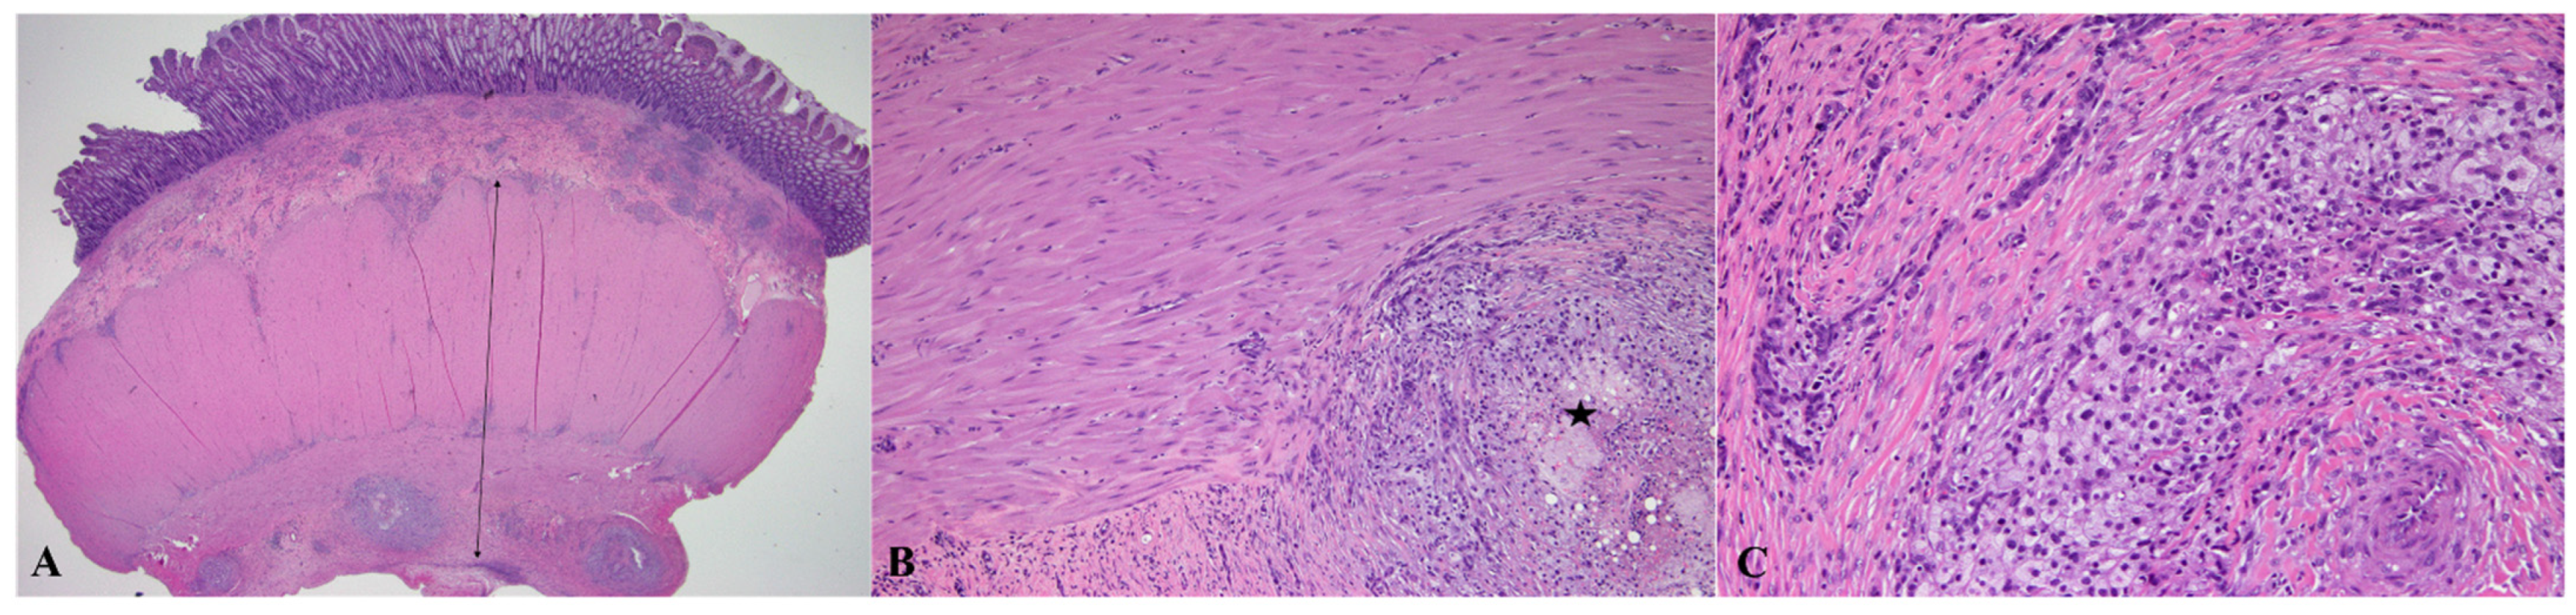

2. Case Description